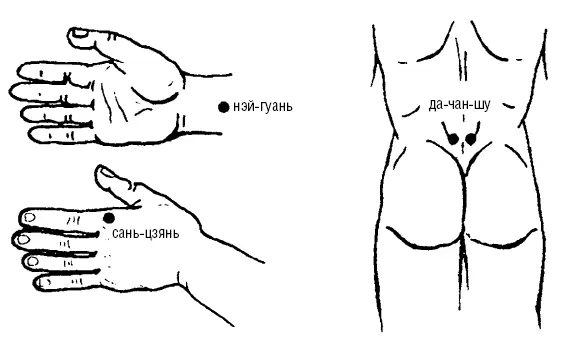

Рис. 111. При поносах (диарее)

Методика точечного массажа седативная, расслабляющая, успокаивающая (рис. 111):

1. ДА-ЧАН-ШУ (V-25) находится на 1-й линии спины между L 4_ 5/1, на расстоянии 1,5 цуней наружу от срединной линии спины.

4. САНЬ-ЦЗЯНЬ (GI-3) находится на лучевом крае кисти, на стороне пястнофалангового сустава второго пальца, пальпируется при сгибании кисти на уровне складки.

5. НЭЙ-ГУАНЬ (МС-6) находится на 2 цуня от ближней (проксимальной) складки лучезапястного сустава по направлению к локтевому суставу в нижней трети предплечья внутренней поверхности.